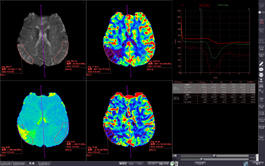

MR BRAIN PERFUSION

Analyzes blood flow using contrasted MR images scanned at the same cross-section, showing changes over time.